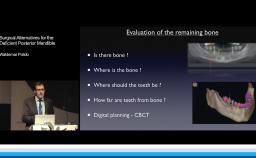

Many complications can be avoided by identifying and managing systemic and local risk factors before grafting is performed. As more bone grafting materials and techniques are available and being performed by a larger number of clinicians, complications must be identified and managed early and thoroughly. This lecture will highlight risk factors associated with increased postoperative complications in bone augmentation procedures, and discuss the most frequent complications associated with horizontal and vertical grafting with implant placement.

- recognise the risk factors/risk indicators associated with the occurrence of these complications and which are the critical factors in their prevention